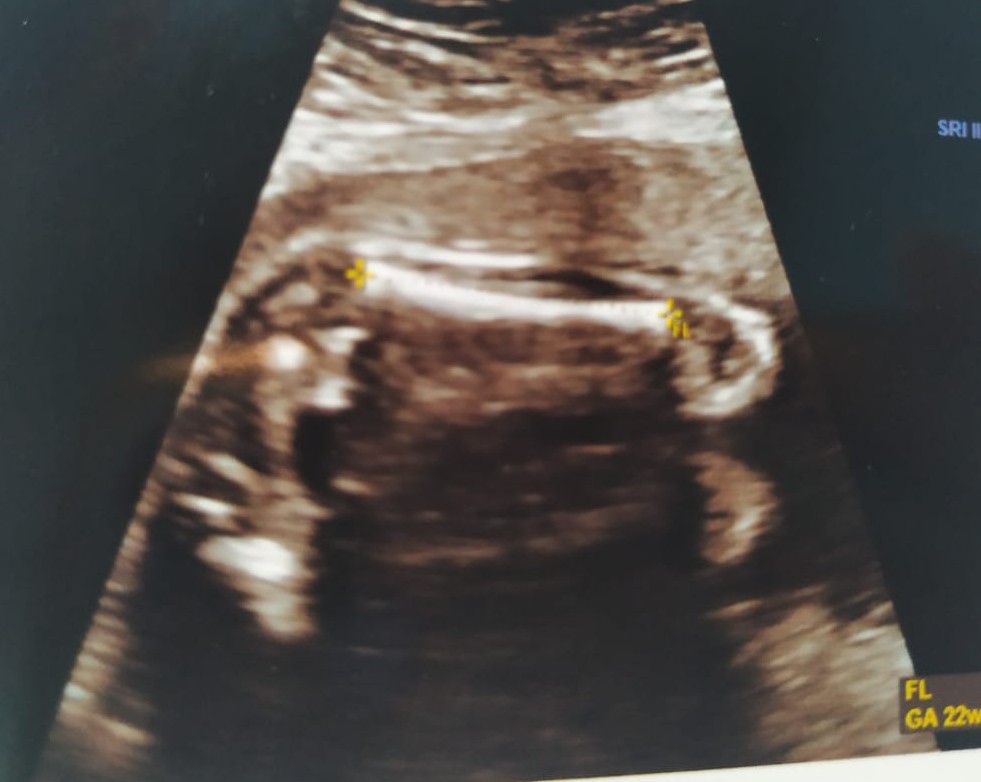

I am not sure if I am seeing it correctly but could the circled portion be genitals?

Attachment 42235

It could be but it's too blurry and dark to tell what it is.